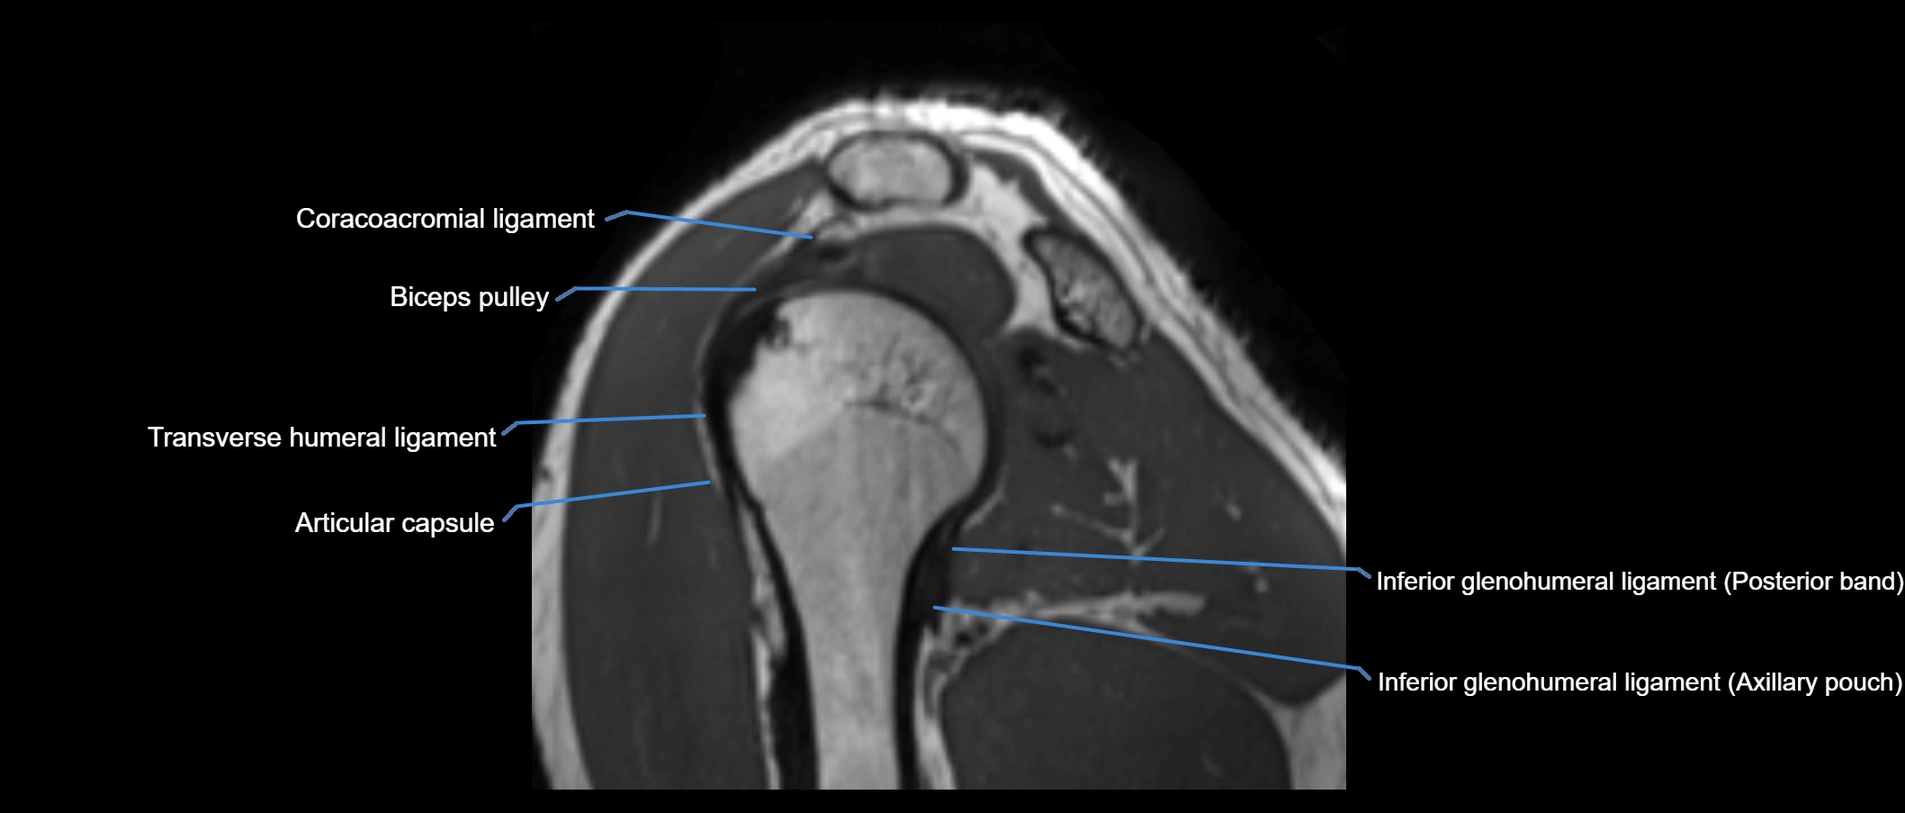

CT image

image